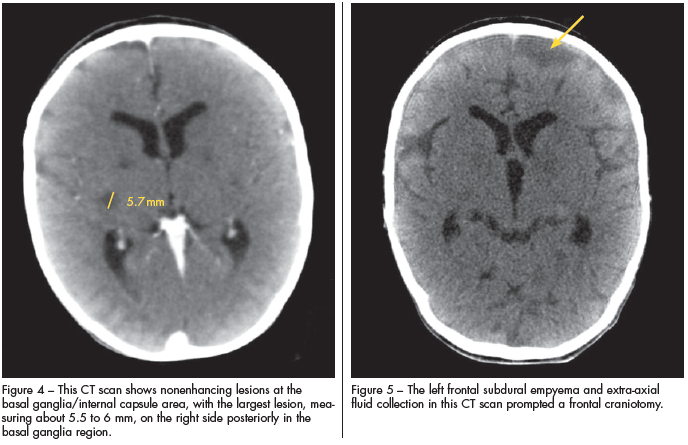

The child appeared to improve clinically, until day 3 when seizures began. Repeated CT studies showed nonenhancing lesions at the basal ganglia/internal capsule area, with the largest lesion on the right side posteriorly in the basal ganglia region measuring about 5.5 to 6 mm (Figure 4). A left frontal subdural empyema and extra-axial fluid collection (Figure 5) prompted a frontal craniotomy for evacuation.